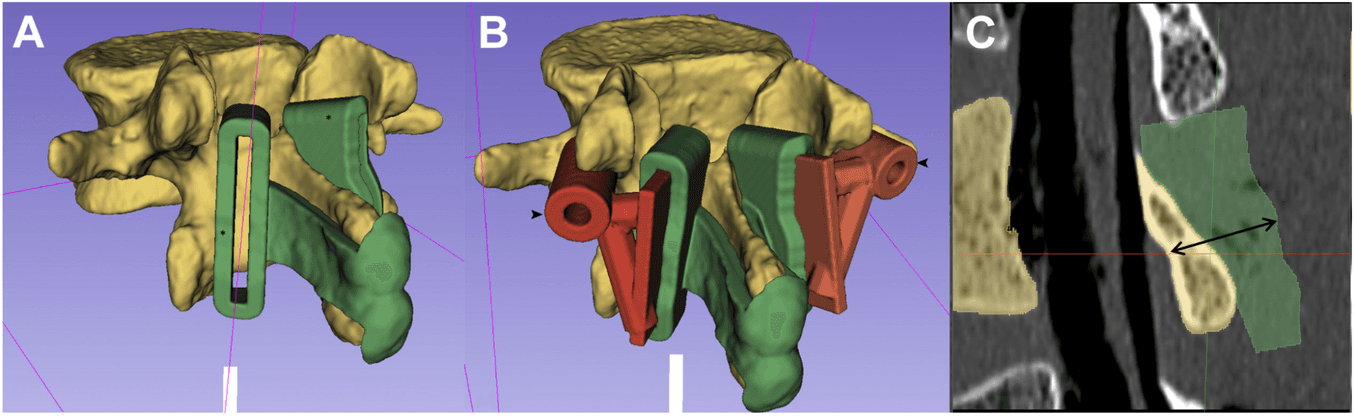

(A) A vertebral model and laminectomy guide were created using 3D Slicer. (B) Drill guides (arrowhead) were created and joined to removable slots, which fit into the laminectomy guides, to create a 2-in−1 guide. (C) Sagittal reconstruction demonstrating the 14-mm depth-stop design (double arrow). The dorsal contour of the laminectomy guides was created to match the deep surface of the lamina, set at a depth of 14 mm.

“This was a cadaveric study designed to test novel 2-in-1 patient-specific laminectomy guides, with modular removable pedicle screw drill guides… Computed tomography (CT) scans of 3 lumbar spines were imported into 3D Slicer. Spinal models and patient-specific guides were created and 3D printed… using Formlabs Form 2 (Formlabs Inc.) desktop 3D printer using Grey Pro Resin (Formlabs Inc.). The bones were cleaned to visualize and record the under surface of the lamina during laminectomy. Pedicle screws and laminectomies were performed with the aid of patient-specific guides. CT scans were performed to compare planned and actual screw and laminectomy positions.”

Results

“Thirty screws were inserted in 15 lumbar vertebrae by using the integrated 2-in-1 patient-specific drill guides. There were no cortical breaches on direct examination, or on postoperative CT. Digital video analysis revealed the burr tip did not pass deep to the inner table margin of the lamina in any of the 30 laminectomy cuts. Average surgical time was 4 minutes and 46 seconds”